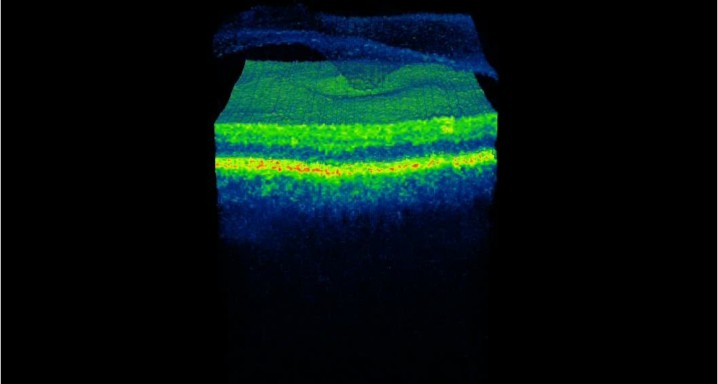

Como consecuencia de esta tracción sobre la mácula, puede originarse un cúmulo de líquido (edema macular cistoide) o la separación de las capas de la retina (retinosquisis macular) o incluso la formación de agujeros en la mácula, que conllevan pérdida de visión.

· Tomografía de coherencia óptica